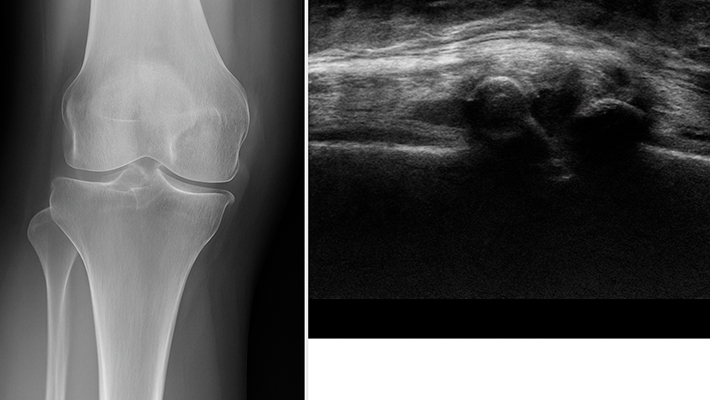

УЗИ — метод, основанный на свойствах ультразвуковых волн. Они с разной частотой отражаются от тканей разной плотности. Благодаря этому эффекту на мониторе визуализируются ткани и структуры, через которые проходят волны. Врач видит, в каком состоянии находятся связки, сухожилия, мениски, суставная капсула и другие структуры колена. УЗИ помогает обнаружить воспаления, скопление жидкости, повреждения мягких тканей и другие важные параметры.

Важно! Кости на УЗИ видны плохо, но все, что мягче кости — хорошо визуализируется. Поэтому ультразвук не заменяет рентген или МРТ, но становится главным методом при обследовании мягкотканных структур. Именно они чаще всего становятся источником боли и ограничений подвижности.

- Сканирование. Врач водит датчиком по поверхности колена — спереди, сзади и с боков. Устройство отправляет ультразвуковые сигналы вглубь тканей и получает отраженные волны, которые превращаются в изображение на экране. Специалист внимательно изучает связки, сухожилия, мениски, суставную капсулу и синовиальную оболочку. При необходимости исследование проводится и в движении — пациент может сгибать и разгибать ногу.